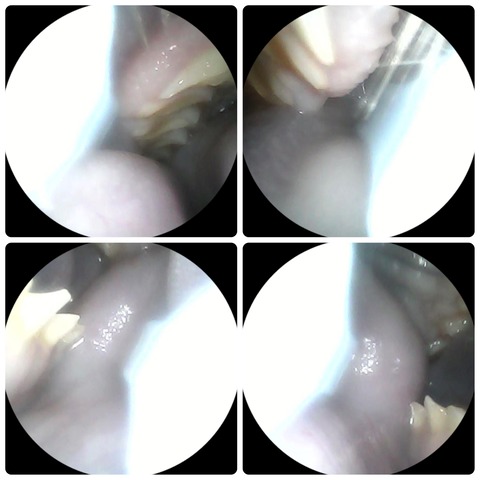

上顎の臼歯は頬側に、下顎の臼歯は舌側に伸びる傾向にあります

(それぞれ上下左右の臼歯)

特に下顎の臼歯は正常でもかなり舌に向かって鋭く尖ってるように見えますが、これで正常です

臼歯は、噛み合わせが悪いせいで摩耗せずに過長すると、舌や頬粘膜に刺さってかなりエグることがあります

(右下顎臼歯が舌に刺さって傷つけていた、カット後の様子)

(頬粘膜側に伸びていた右上顎臼歯の棘をカットしたビフォーアフター)